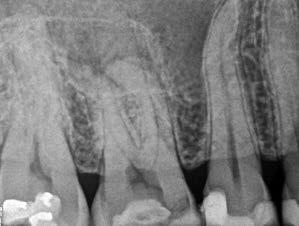

Esetbemutatás (1.)

Egy 63 éves páciens korábban már kezelt bal alsó első nagyőrlőfogából (3.6) eredő mérsékelt fájdalom miatt kereste fel rendelőnket. A kórtörténetében panasza szempontjából releváns információ nem szerepelt. Az elkészült CBCT-felvételen a korábbi kezelések során észre nem vett, jelenleg feltáratlan meziobuccalis csatornát, valamint a mezialis és distalis gyökerek körül kialakult periapicalis elváltozást, és ezt a léziót borító intakt buccalis corticalis csontlemezt láttunk.

A fog revideálását és újbóli gyökértömését két ülésben végeztük el. A régi gyökértömés eltávolítását, valamint mindhárom gyökércsatorna megmunkálását és fertőtlenítését követően kalcium-hidroxid alapú gyógyszeres zárást helyeztünk a gyökércsatornákba. A gyökértömés egy héttel később került behelyezésre. A páciens panaszai két hónap elteltével sem szűntek.

Klinikai vizsgálat során vertikális kopogtatási érzékenységet jelzett. A fog körül mérhető szondázási mélység és a fogmobilitás fiziológiás volt. A CBCT-felvételen nem észleltünk a csontos regeneráció megindulására utaló jeleket (1. a–c. ábrák). A korábban gyökérkezelt, gyökértömött és revideált 3.6-os fog esetében az alábbi diagnózis került felállításra: periodontitis periapicalis symptomatica. A panaszokat okozó fog további ellátása során navigált endodonciai mikrosebészetet kívántunk alkalmazni. Az alsó állcsontról intraorális szkent (TRIOS, 3Shape) készítettünk, és a felszíni topográfiát tartalmazó STL fájlt, valamint a CBCT-felvétel készítése során nyert DICOM fájlokat a Blue Sky Bio szoftver segítségével egyesítettük. A sebészi sablon megtervezésére az így kapott háromdimenziós képet használtuk. A sablon kialakítása során arra törekedtünk, hogy a sablon egyértelműen meghatározza a gyökércsúcsi terület eléréséhez szükséges csontablak határait (1. d. ábra)